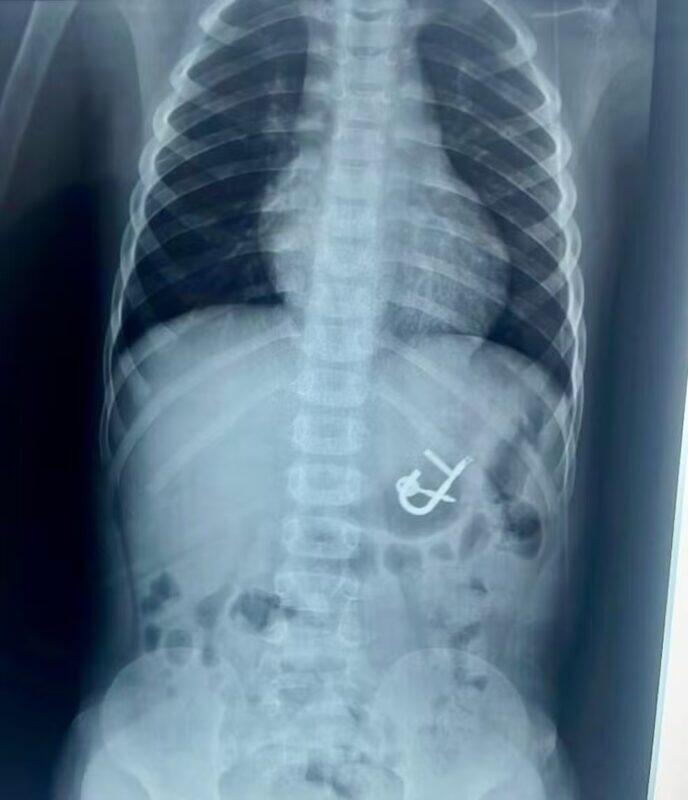

Uma criança de quatro anos engoliu um cadeado com as chaves em Cedro, no Sertão de Pernambuco. O menino deu entrada no último sábado (10) no Hospital Regional Inácio de Sá, em Salgueiro. O objeto foi retirado com sucesso, no mesmo dia, por meio de endoscopia digestiva, e o paciente já teve alta médica.

“Quando eu cheguei no raio x, já dava para ver que o cadeado estava no estômago. A nossa maior preocupação era o tempo de passar e esse cadeado progredir para o intestino, porque provavelmente ocasionaria uma obstrução intestinal, e realmente teria que ser cirúrgico. Então, rapidamente fomos para o bloco cirúrgico para fazer a anestesia da criança. O cirurgião Nairton estava a postos, se durante a retirada houvesse lesão no esôfago e precisasse de cirurgia de urgência. Felizmente, deu tudo certo, nós realizamos a retirada em aproximadamente 20 minutos”, explicou.